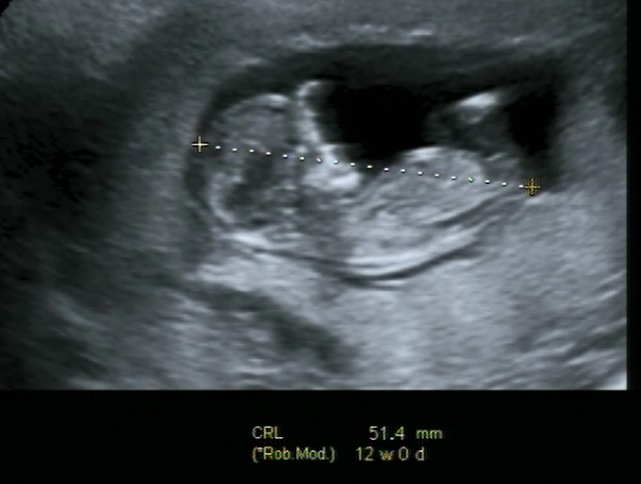

11 weeks and 6 days.Attachment 20230Attachment 20229